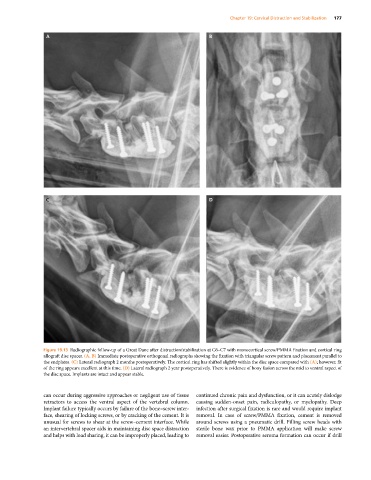

Figure 19.13 Radiographic follow‐up of a Great Dane after distraction/stabilization at C6–C7 with monocortical screw/PMMA fixation and cortical ring

allograft disc spacer. (A, B) Immediate postoperative orthogonal radiographs showing the fixation with triangular screw pattern and placement parallel to

the endplates. (C) Lateral radiograph 2 months postoperatively. The cortical ring has shifted slightly within the disc space compared with (A); however, fit

of the ring appears excellent at this time. (D) Lateral radiograph 2 year postoperatively. There is evidence of bony fusion across the mid to ventral aspect of

the disc space. Implants are intact and appear stable.